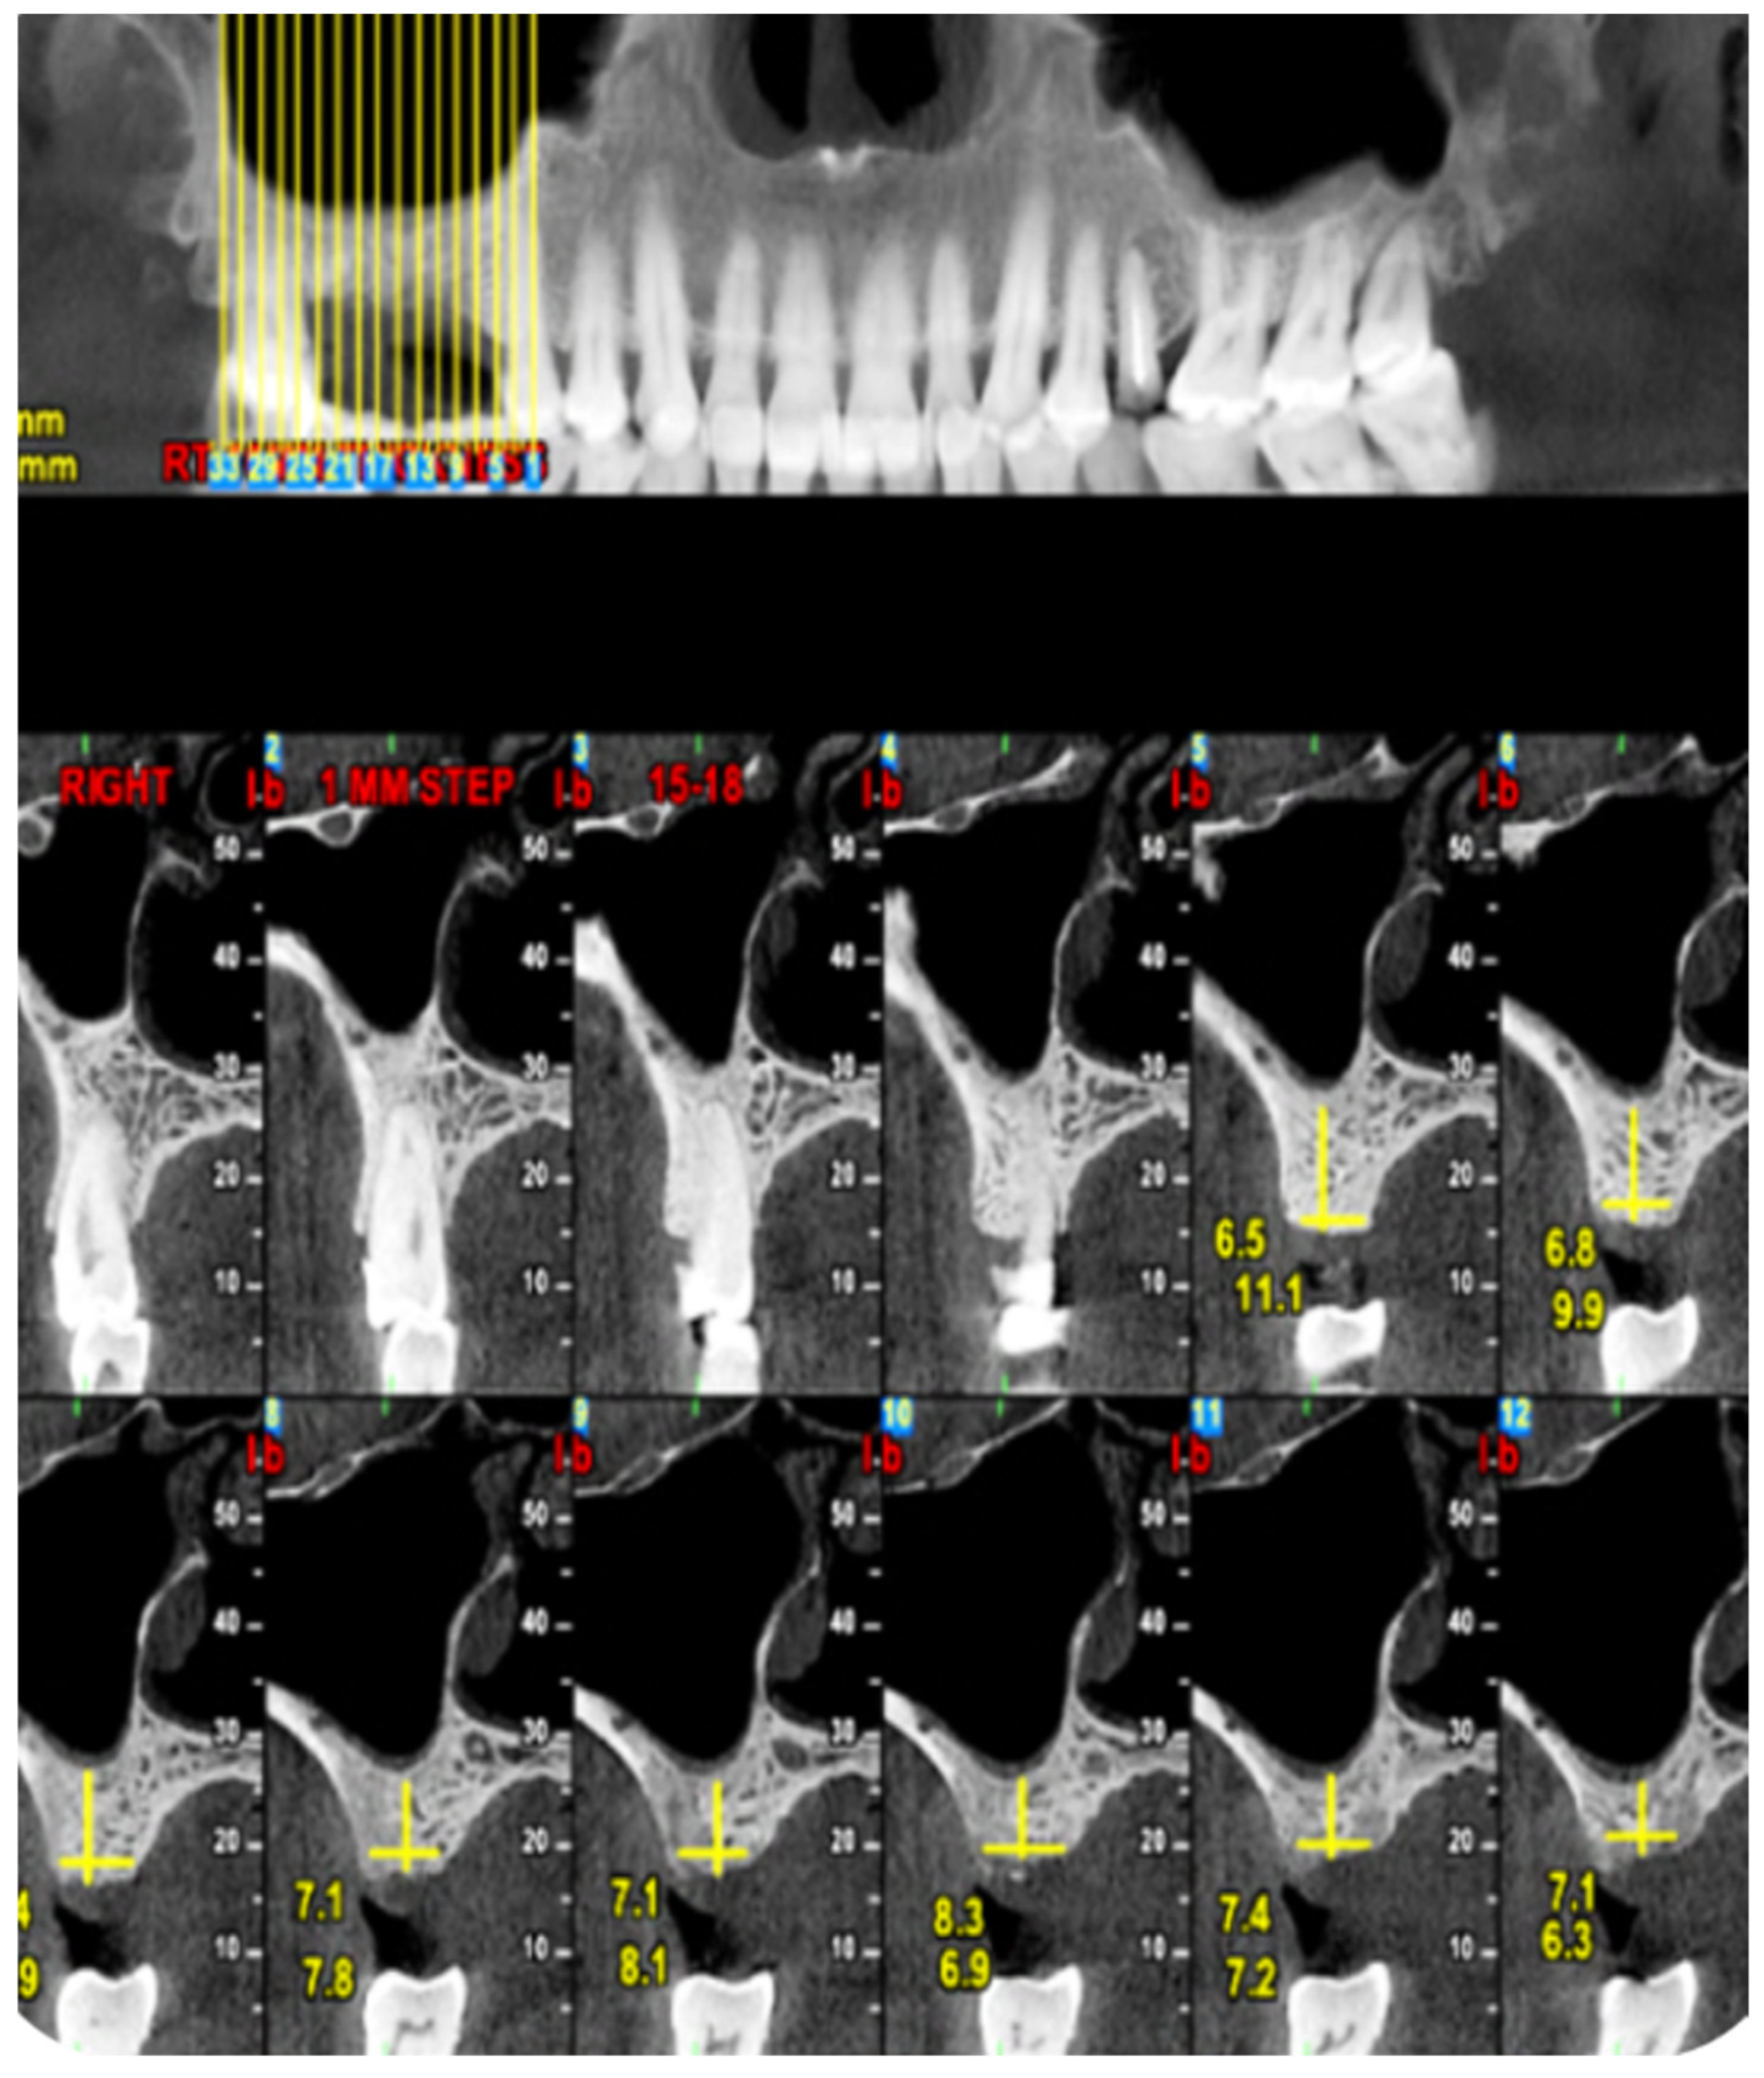

2.1. Standard Surgical Procedure